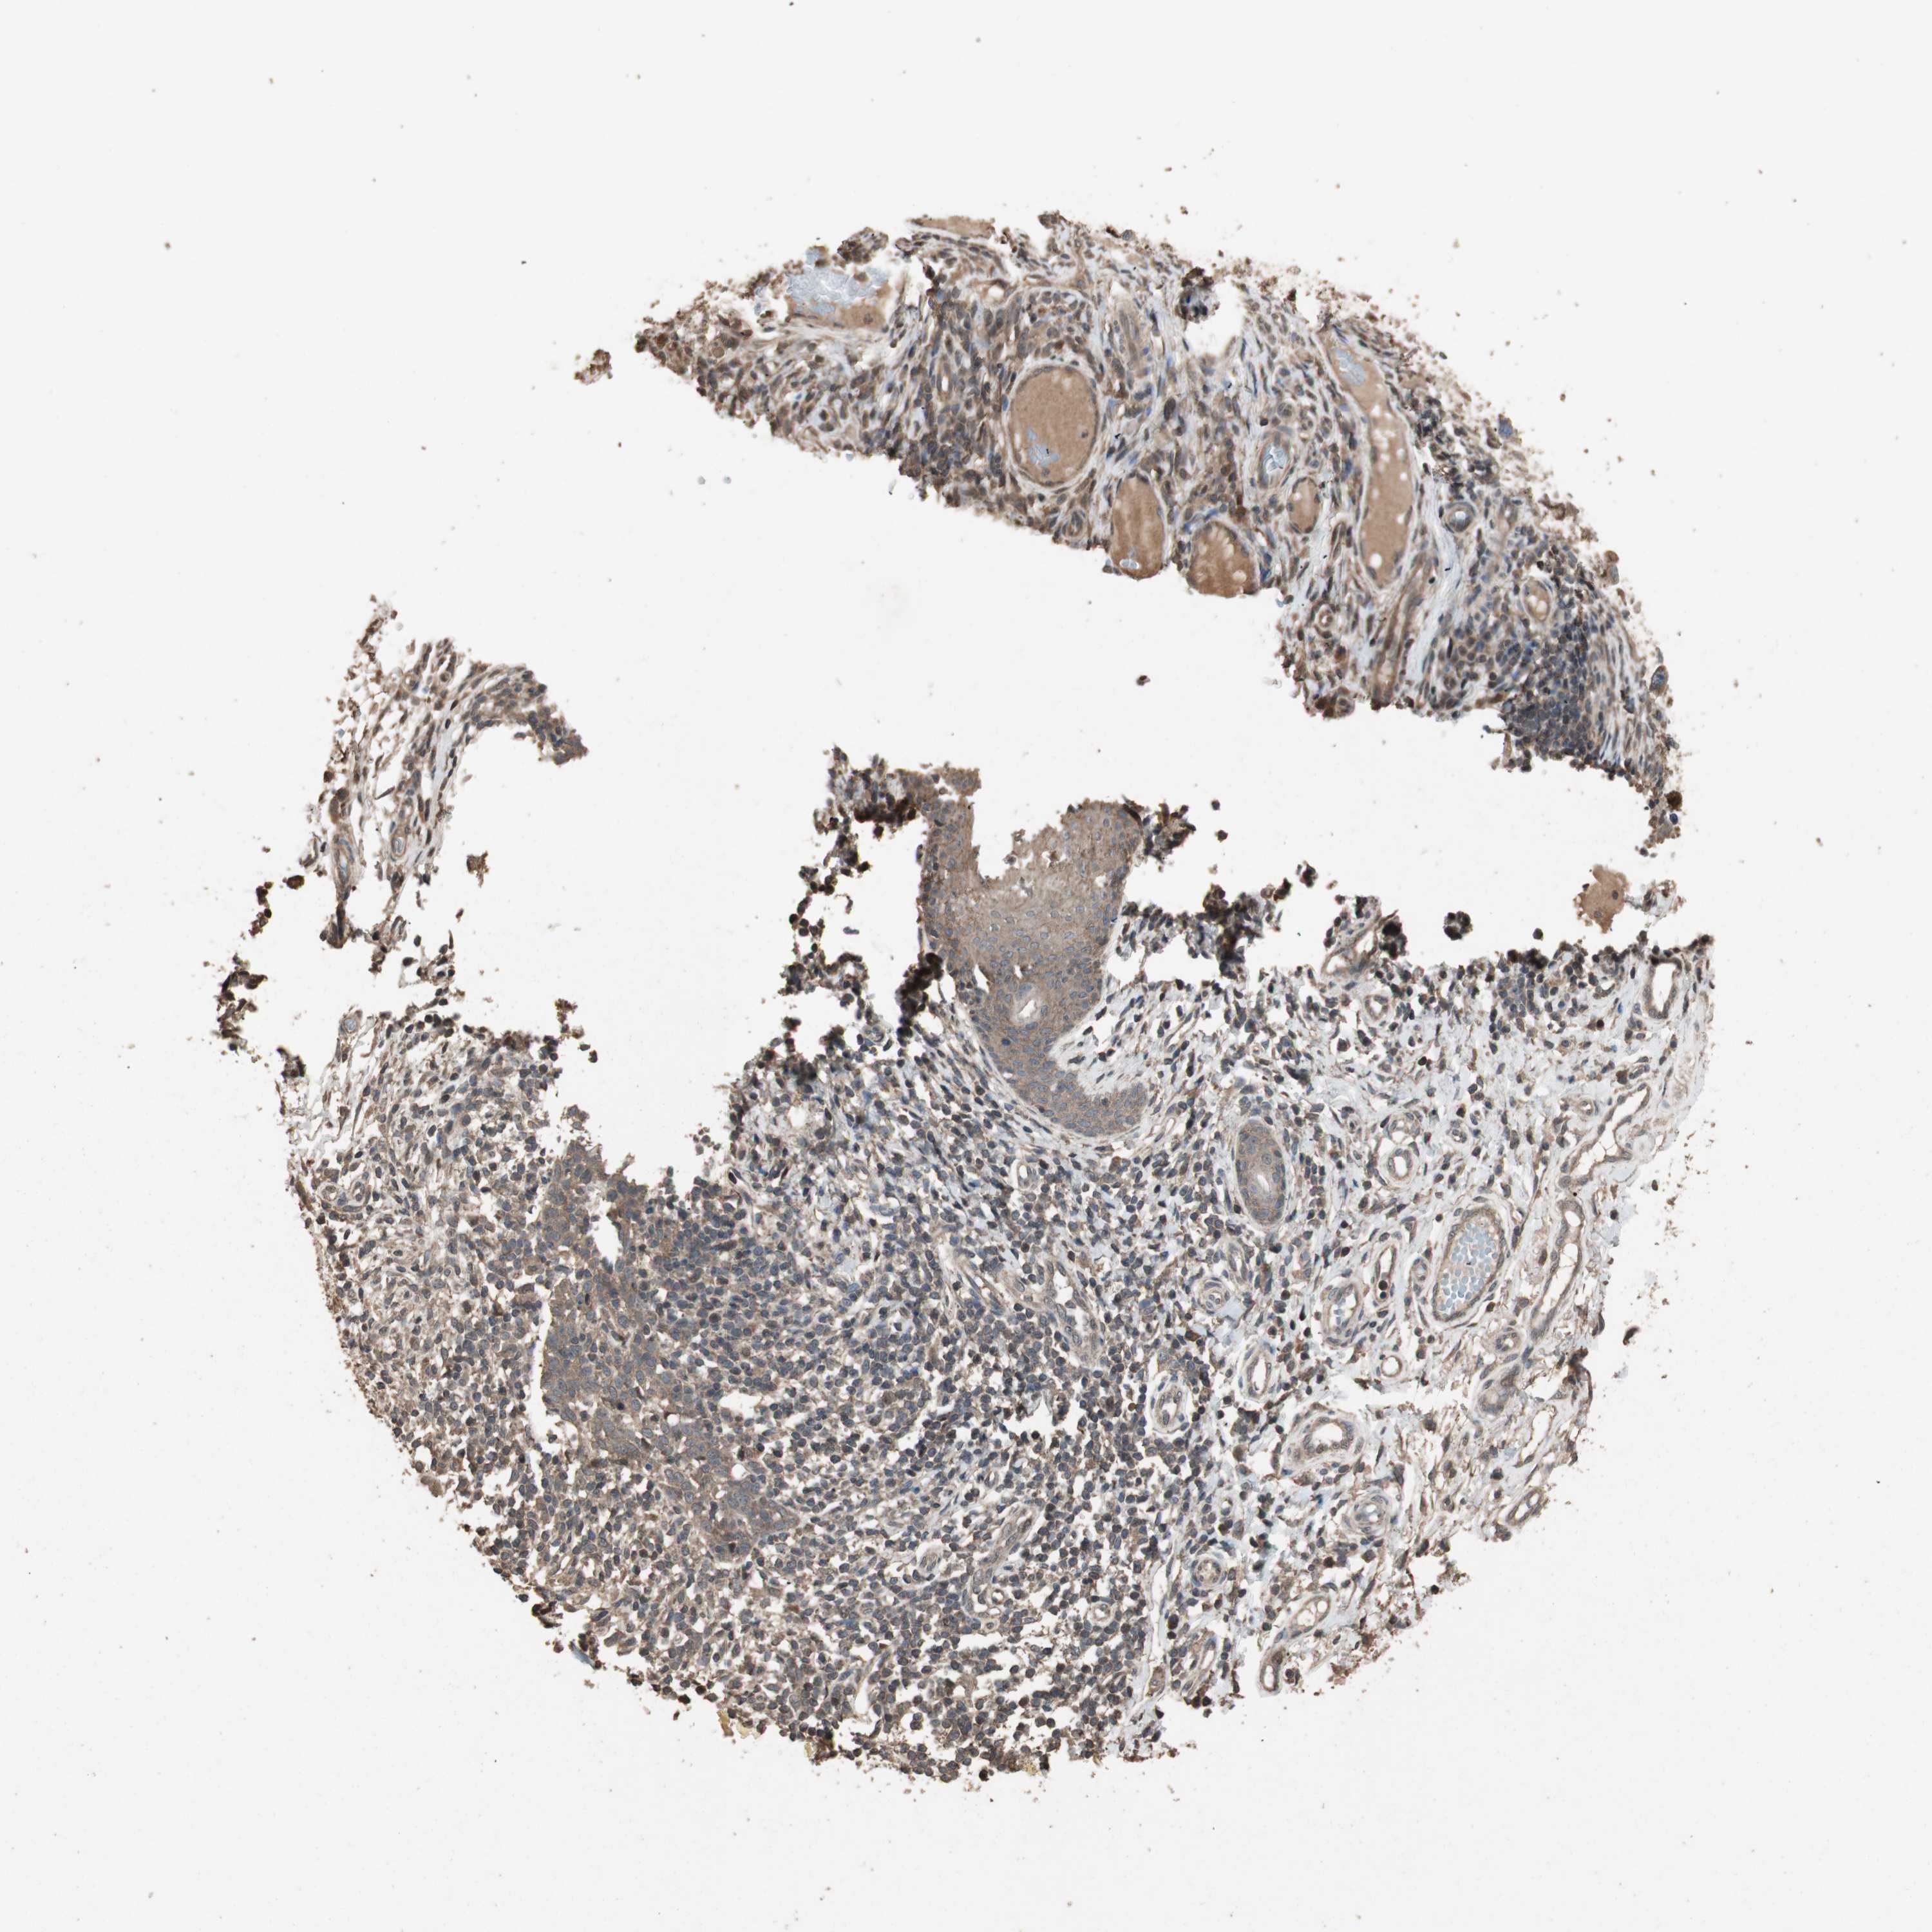

Basal cell and squamous cell cancer

SKIN CANCER - Protein expressioni

A mouse-over function shows sample information and annotation data. Click on an image to view it in a full screen mode. Samples can be filtered based on level of antibody staining by selecting one or several of the following categories: high, medium, low and not detected. The assay and annotation is described here.

Each image is clickable and will lead to virtual microscopy that enables deeper exploration of all samples and also displays staining intensity scores, fraction scores and subcellular localization as well as patient and tissue information for each sample.

Antibody HPA006287

Staining

High

Medium

Low

Not detected

Intensity

Strong

Moderate

Weak

Negative

Quantity

>75%

75%-25%

<25%

None

Location

Nuclear

Cytoplasmic/membranous

Cytoplasmic/membranous,nuclear

Squamous cell carcinoma, NOS

Squamous cell carcinoma, metastatic, NOS

Basal cell carcinoma